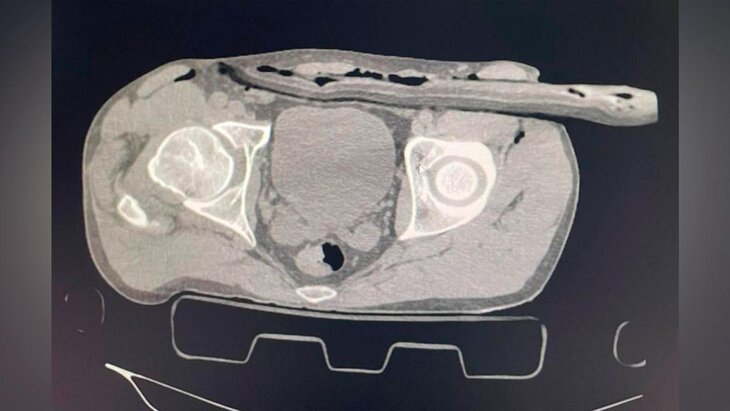

В Солнечногорской больнице спасли мужчину, упавшего с крыши на ветку дерева, рассказали в пресс-службе подмосковного Минздрава.

Пострадавший ремонтировал крышу загородного дома без страховки и упал на сук. Ветка прошла через бедро в толщу брюшной стенки. В больнице ему сделали компьютерную томографию и УЗИ, которые показали наличие свободной жидкости в животе.

Врач-хирург Солнечногорской больницы Иван Балычев отметил, что ветка не задела важные артерии и органы брюшной полости. В ходе операции, которая длилась около часа, медики ушили дефект в брюшине, провели ревизию органов брюшной полости, а также сделали дренаж раневого канала.